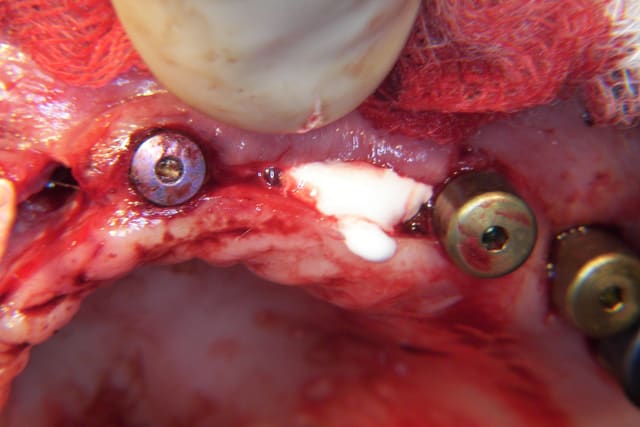

juste pour le plaisir

1- section

2- expansion

3- implants (anthogyr coniques)

4- Vitalos

Du VitalOs et du sang (beurk)!

Perso je ne faits pratiquement que de l’expansion et très peu d’apposition